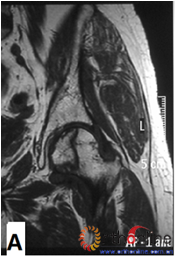

图2 依据股骨头外侧柱存留情况,股骨头坏死的分型。(图2-1)分为Ⅰ型(外侧柱全部存留)(A)MRI图像显示;(B)7年后CT显示股骨头仍未塌陷;(图2-2)Ⅱ型(外侧柱部分保留)(A)MRI显示外侧皮质存留;(B)4年后CT显示股骨头仍未塌陷;(图2-3)Ⅲ型(坏死带穿透股骨头);(A)MRI显示坏死带;(B)2年后股骨头塌陷

Fig 2 According to preservation of the lateral pillar, the necrosis was divided into three types. (Fig 2-1)Type Ⅰ: Whole lateral pillar preserved (A) MRI showing; (B) no collapse occurred seven years later by CT showing. (Fig 2-2)Type Ⅱ: Preservation of the partial lateral pillar, (A) MRI showed the preservation of the lateral cortical bone; (B) no collapse of the femoral head four years by CT. (Fig 2-3)Type Ⅲ: the necrotic line pass through the cortical bone and bone morrow ;(A) MRI showed the necrotic line; (B) collapse of the femoral head occurred two year later.

图3 各型坏死打压植骨的结果,(A)Ⅰ型(右侧)和Ⅱ型(左侧)术前MRI显示外侧柱存留;(B)术后7年随访,股骨头维持外形,关节功能好;(C)Ⅲ型(双侧)术前MRI显示外侧柱破坏;(D)术后5年,右侧股骨头维持外形,左侧塌陷

Fig 3 The results of different osteonecrotic type by impacting bone graft,(A)Type Ⅰ(right),type Ⅱ(left) MRI showed the preservation of the lateral pillar preoperatively; (B) Seven years after operation, the femoral head still maintain sphere, hip function is excellent; (C) Type Ⅲ (both side) MRI showed the involved of lateral pillar by necrosis; (D)Five years after operation, the femoral head still maintain sphere in right side, collapse occurred in left side.